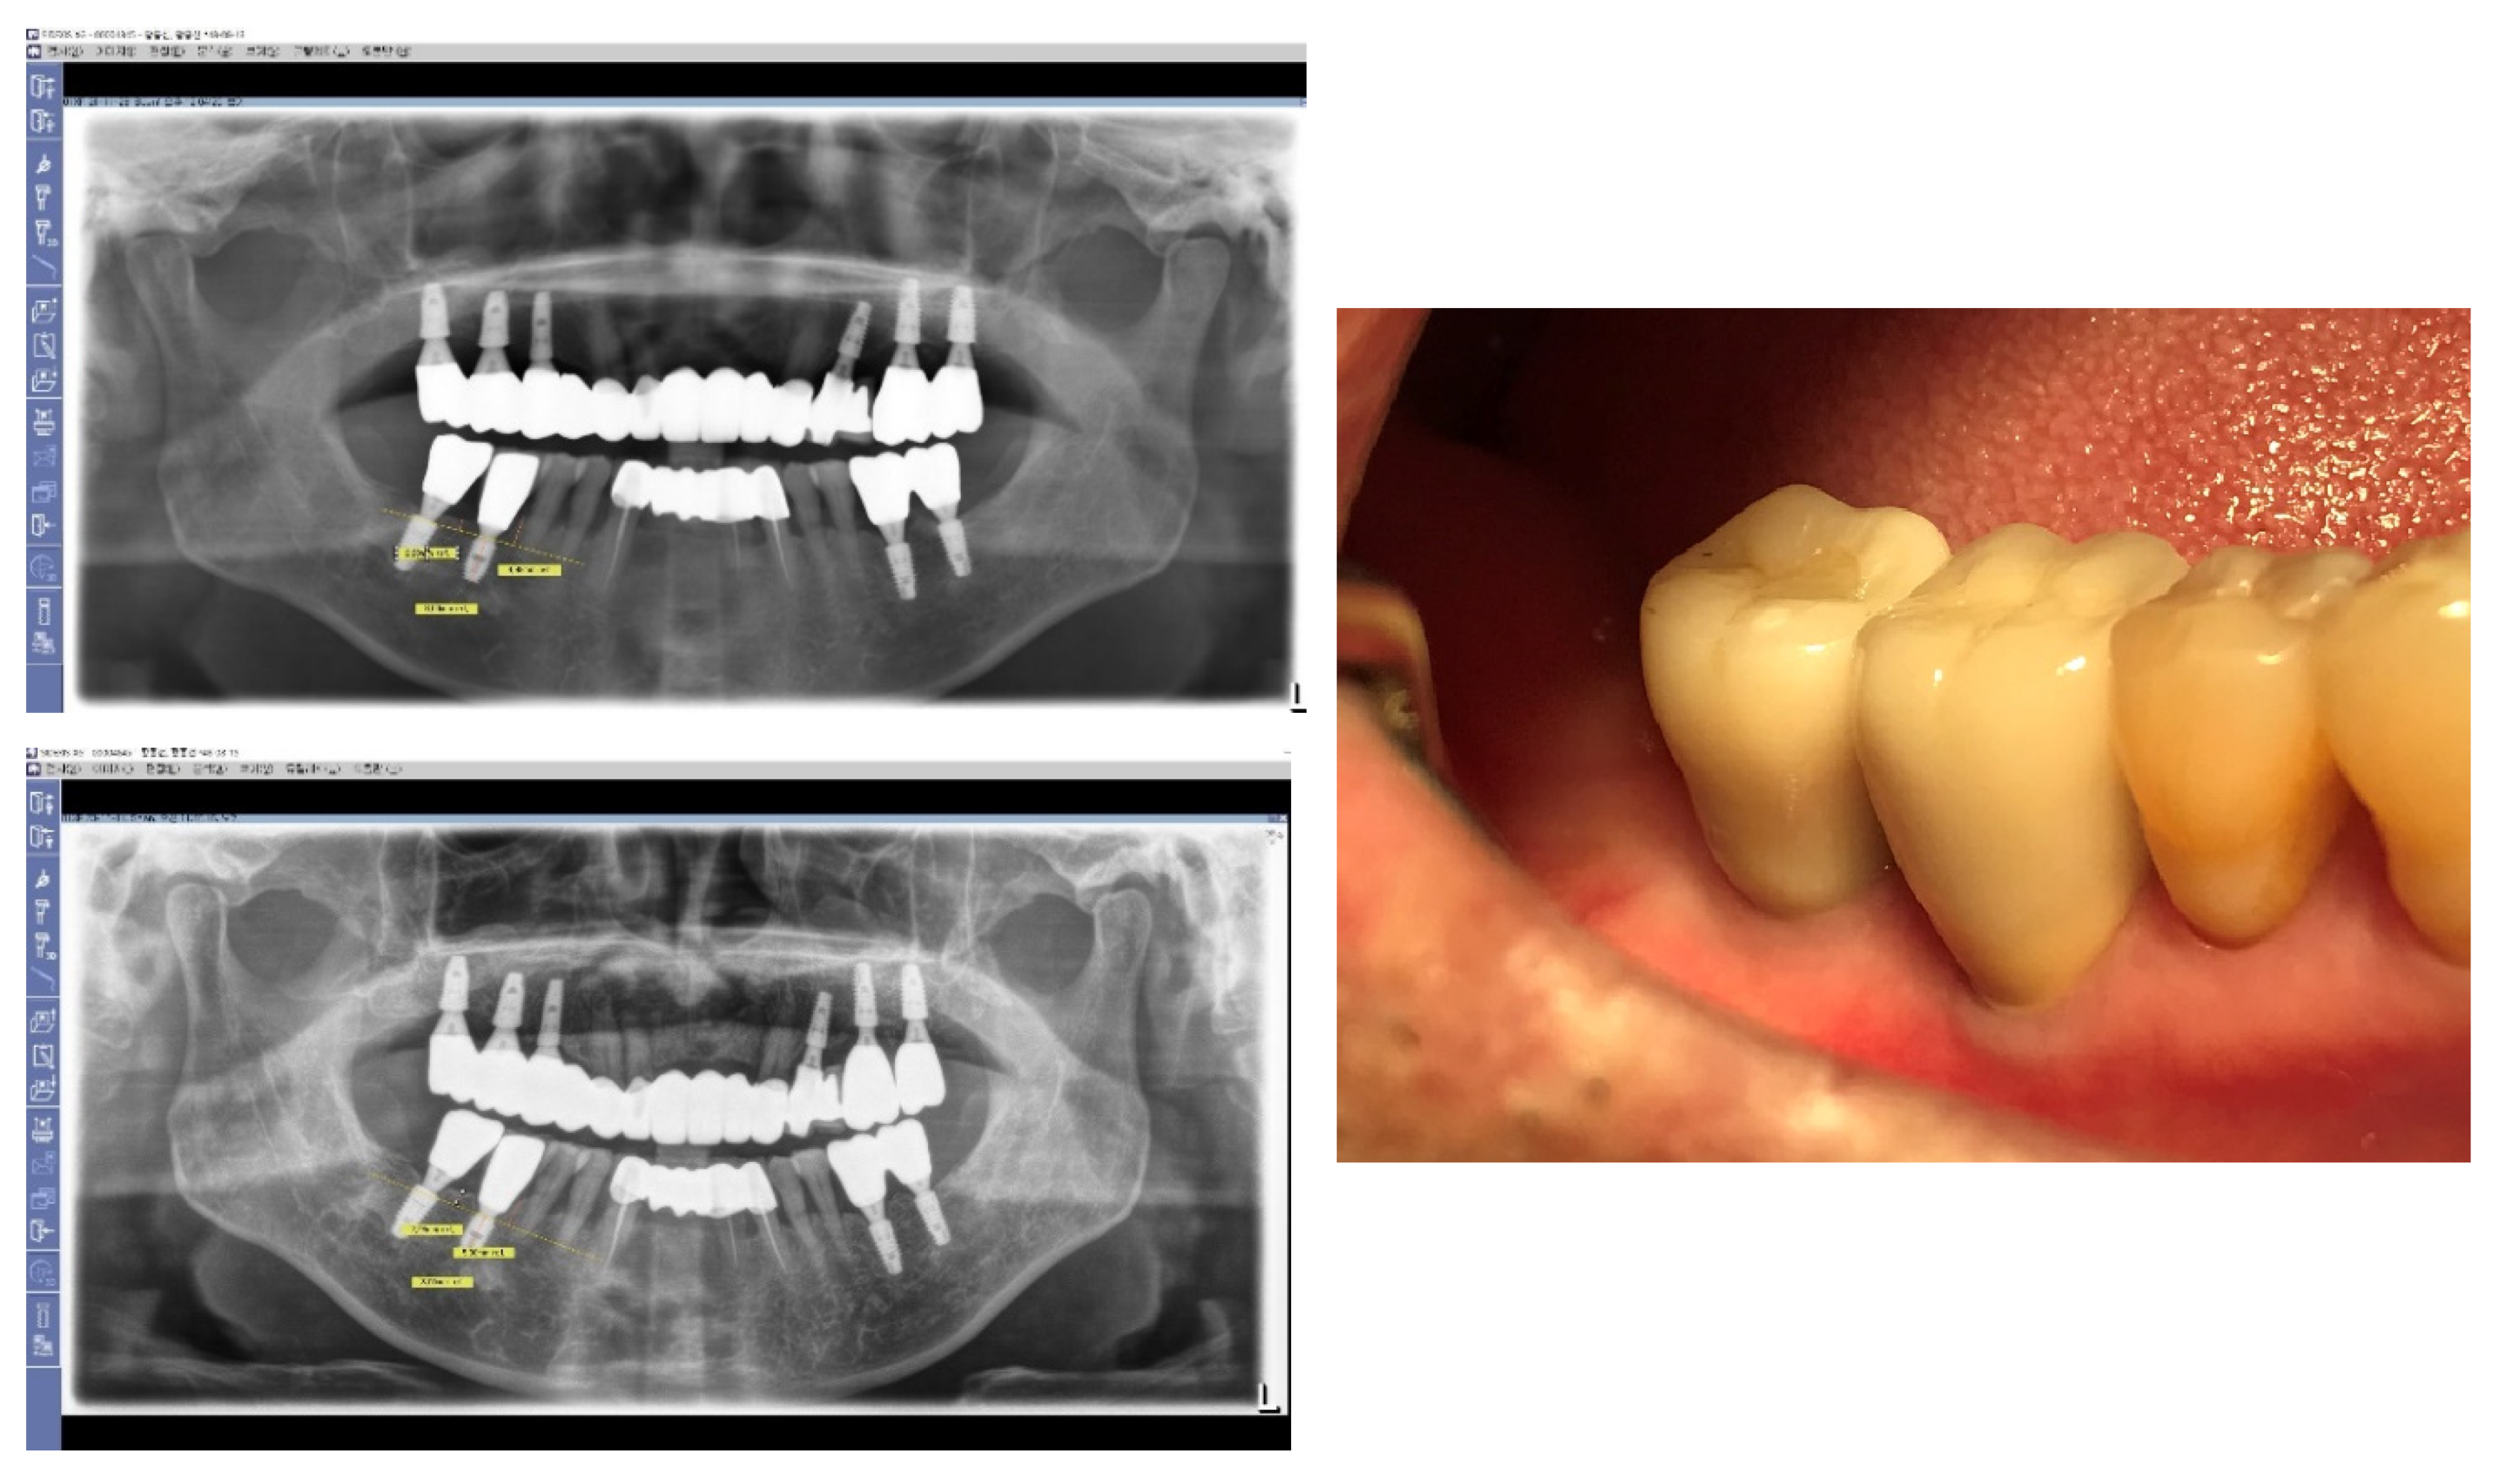

Figure 22. Natural-Looking Results Achieved by SPI Technique. This figure illustrates the effectiveness of the Subcrestally Placed Implants (SPI) technique in achieving results that closely mimic natural teeth. It demonstrates how the biologic width—comprising the transitional zone and subcrestal zone connective tissue—differs from that of natural teeth.